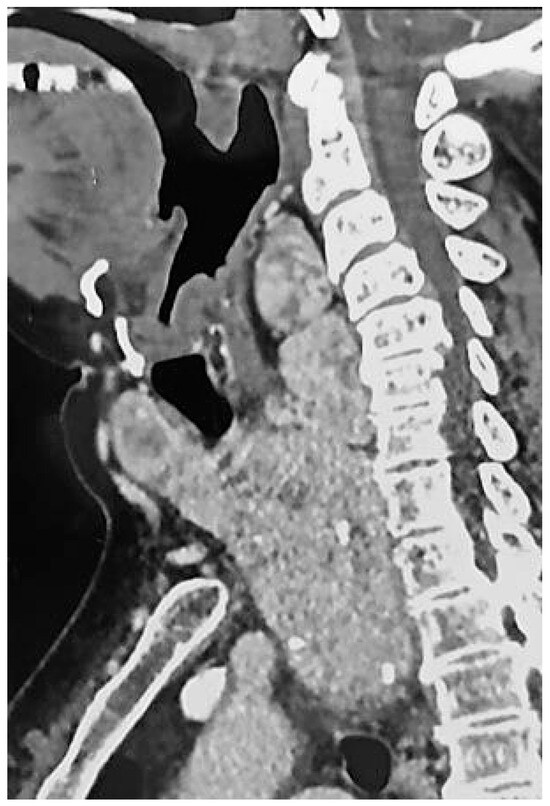

2. Case Description